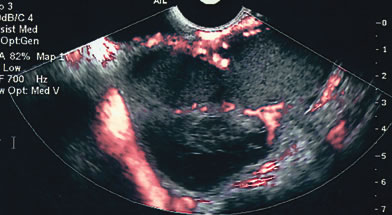

Fig. 4. A complex 12 × 10-cm mass in a premenopausal woman contained multiple septations with solid elements that had marked vascular flow. The mass was correctly identified as malignant (Stage III papillary adenocarcinoma).